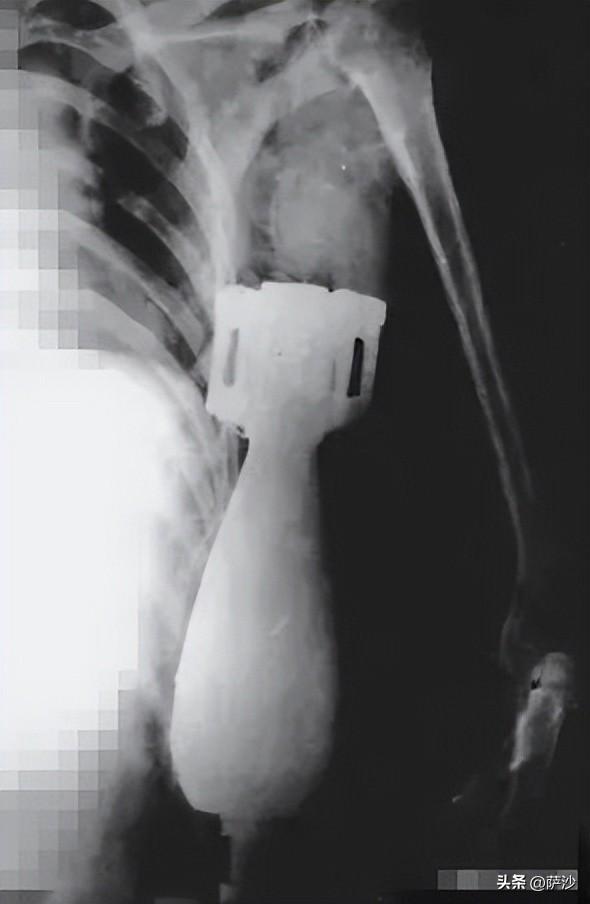

炮彈首先擦碰到了南越士兵阮文良的鋼盔,隨後繼續下墜,從鎖骨和肩膀中間射進了他的身體。直到被胳肢窩下面的肌肉組織兜住,炮彈才停了下來,沒有爆炸。

其他南越士兵搞不清阮文良受了什麼傷,七手八腳的將他送到美國海軍醫院。

於是,外科醫生哈利看到阮文良的X光片以後,第一反應是對護士破口大罵:你知不知道,我每天要做10多個手術,還TMD有心情同我開這種玩笑?炮彈能射入人體內還不爆炸?你以爲是看卡通片?退一步說,就算炮彈沒炸,這人也早就見上帝了,應該送到太平間去。

然後,哈利就看到了病牀上的阮文良,頓時驚呆了:炮彈幾乎沒進了胸腔,就剩下個尾翼露在外面,還不知道什麼時候會爆炸。

哈利硬着頭皮做完了手術,將炮彈取了出來。

阮文良受了這種百萬分之一概率的傷,然而運氣卻不錯,休養了2個月以後大體恢復了健康。